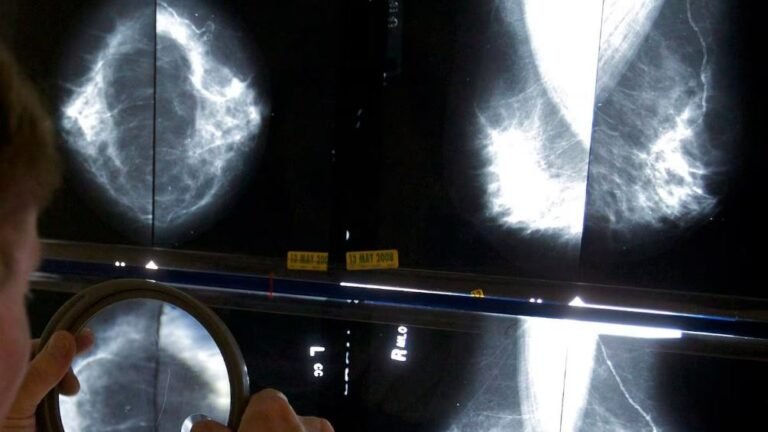

هلا كندا – أظهرت دراسة كندية جديدة وجود فجوة مقلقة في وفيات سرطان الثدي بين النساء ذوي البشرة السمراء والبيض.

وسجلت النساء السود من أصول كاريبية معدلات وفاة أعلى بنسبة تصل إلى 70% في الفئة العمرية الممتدة بين 40 و49 عامًا، وبنسبة 42% بين 50 و59 عامًا.

وقالت الدراسة إن النساء ذوي البشرة السمراء يُصبن بالمرض في سن أصغر، إذ يتراوح متوسط عمر الوفاة بين 53 و66 عامًا، مقابل 71 عامًا لدى النساء البيض.

فيما تُشخّص أكثر من نصف الحالات بين النساء ذوي البشرة السمراء قبل سن الخمسين، مقارنة بـ14% فقط لدى النساء البيض.

وذكرت الطبيبة آنا ويلكنسون أن سرطان الثدي «ليس مرضًا واحدًا»، وأن أنماطه البيولوجية تختلف بين المجموعات، مؤكدة أن النساء ذوي البشرة السمراء أكثر عرضة للإصابة بأنواع عدوانية مثل «الثلاثي السلبي»، الذي يظهر لديهن بنسبة تصل إلى 21% مقابل 9.9% لدى النساء البيض.

وأشارت الدراسة أيضًا إلى أن النساء ذوي البشرة السمراء يُشخّصن بمراحل متقدمة، إذ اكتُشفت 39% من الحالات في المرحلة الأولى لديهن، مقابل 50% لدى النساء البيض.